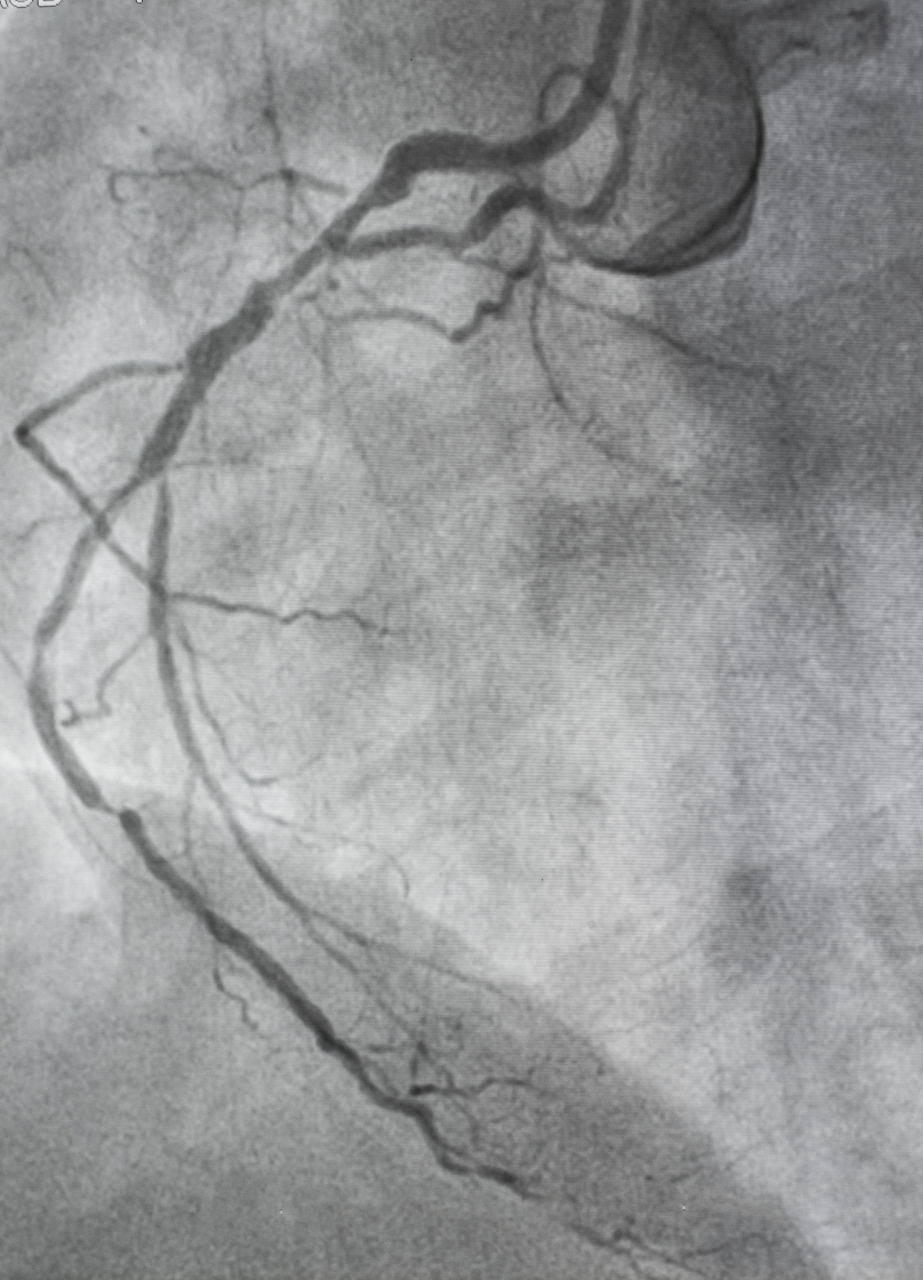

acs患者入院后冠脉造影提示三支严重病变:右冠开口后慢性闭塞

冠脉搭桥术后13年静脉桥血管闭塞急性心梗